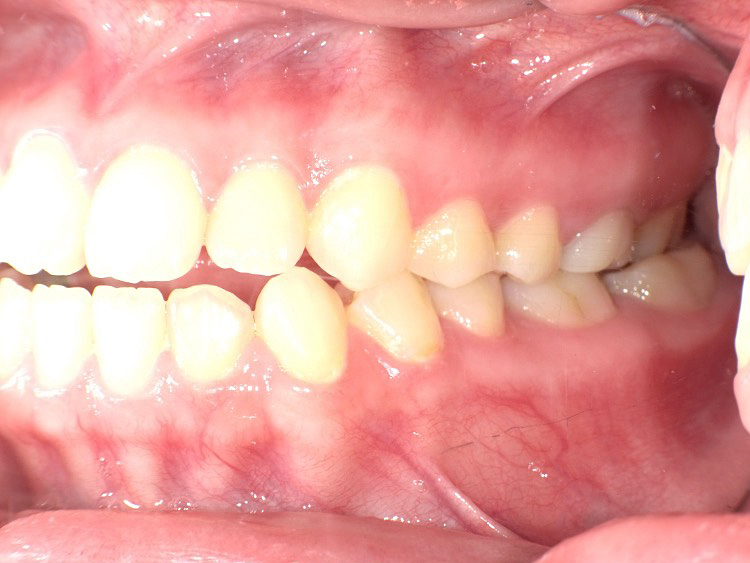

症例3

Before

After

| 主訴 | 上下の歯のガタガタを治したい |

|---|---|

| 年齢 | --- |

| 治療期間 | 約10ヶ月 |

| 治療内容 | インビザラインiGoで上下顎の治療。 狭まっていた歯並びを広げることで、 ガタガタに並んでいた歯を綺麗に並べた。 |

| 治療費 | ¥517,000(税込)+月額調整料 |

| 治療のリスク | 歯と歯の間を削ることでスペースを確保するので、 場合によっては歯が染みる症状が出ることがある。 |